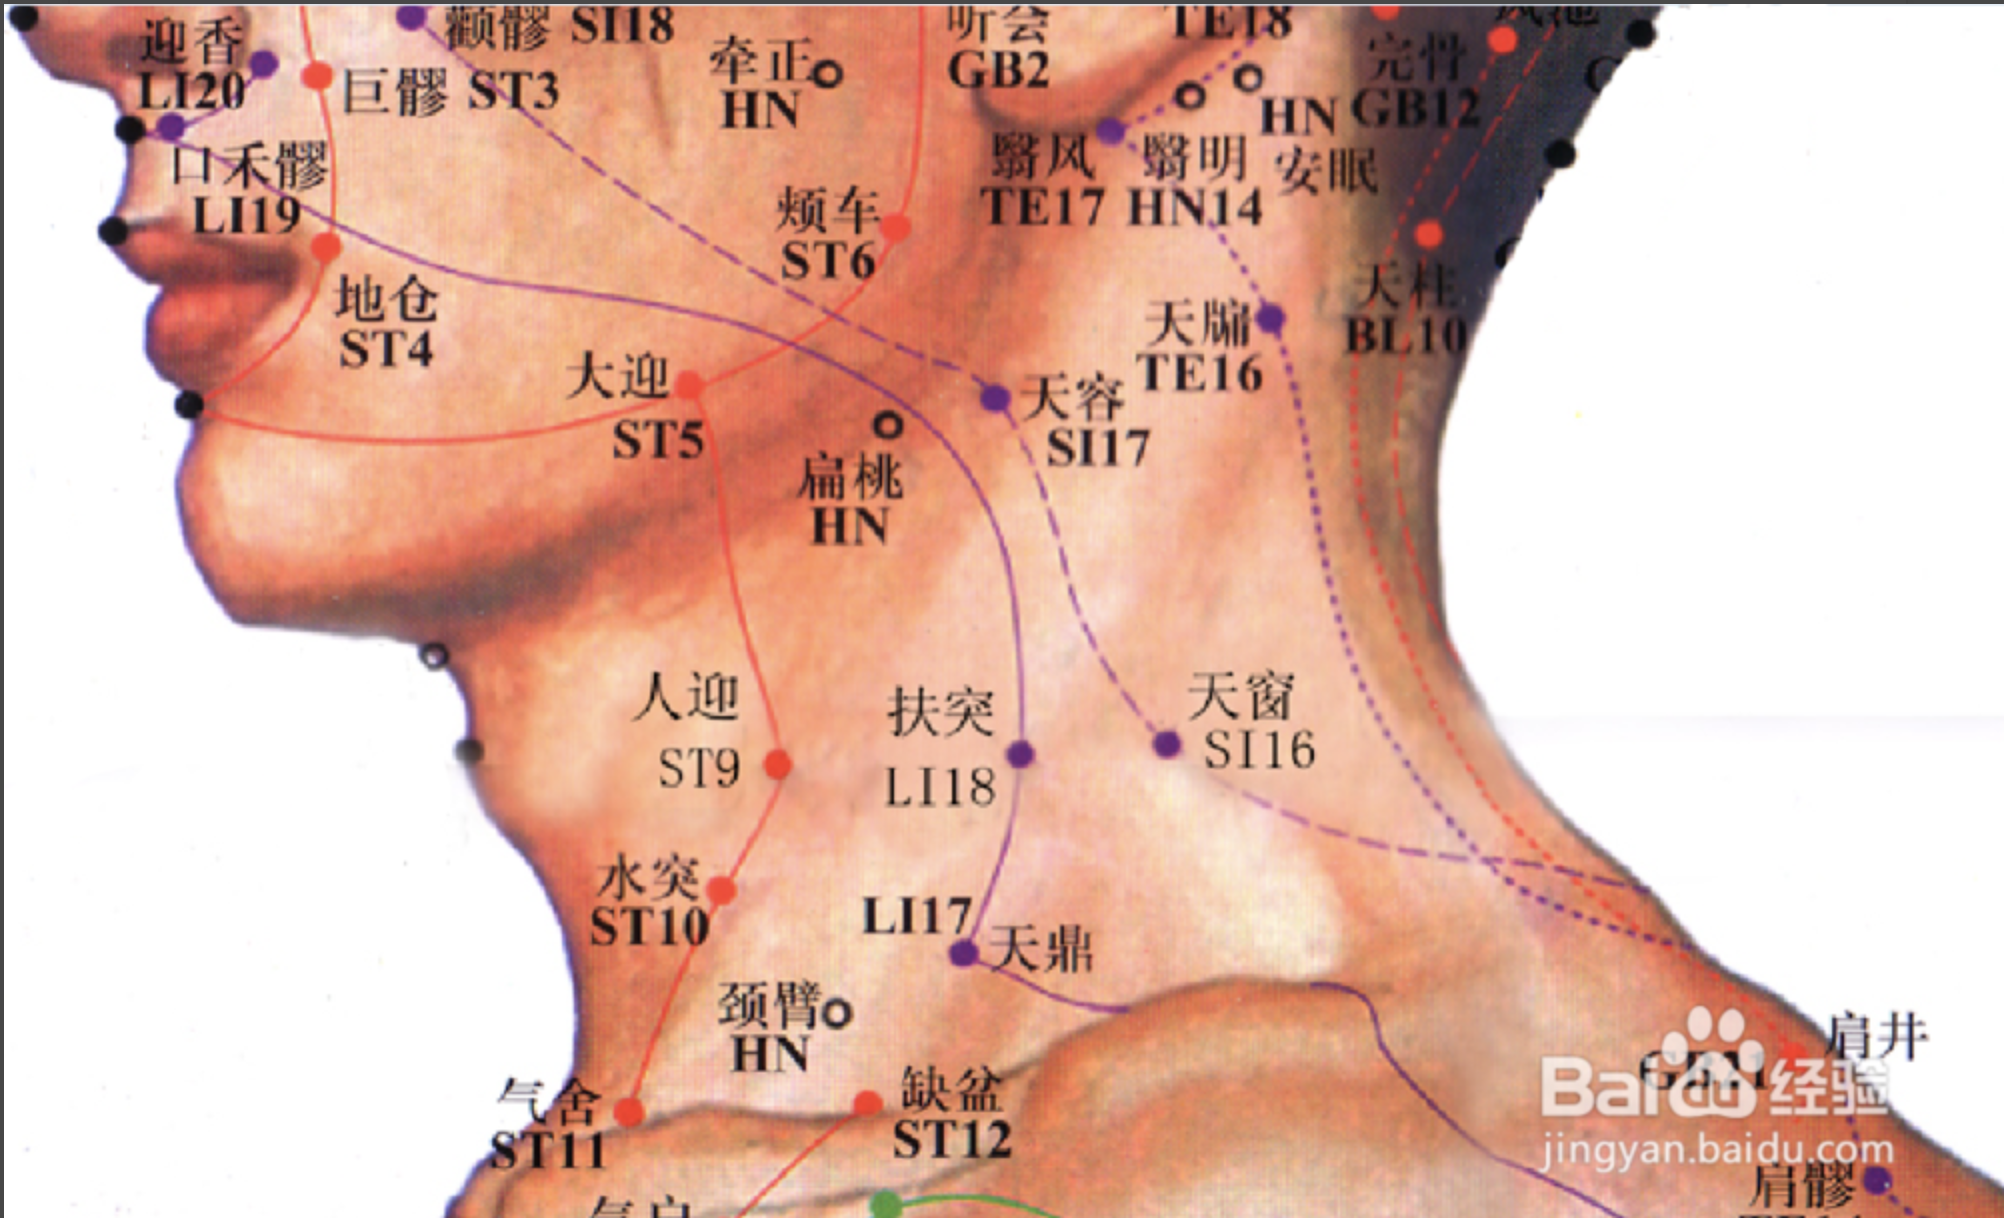

【(二)手阳明大肠经(图10-20-1)】

2、歌诀 手阳明穴起商阳,二间三间合谷藏,阳溪偏历历温溜,下廉上廉三里长,曲池肘髎(liáo)迎五里,臂臑(nào)肩髎(liáo)巨骨起,天鼎浮突接禾髎(liáo),终以迎香二十止。

3、经脉循行 起于食指末端(商阳),沿食指外(桡)侧向上,通过一、二掌骨之间(合谷)向上进入两筋(拇长伸肌腱与拇短伸肌腱)之间的凹陷处,沿前臂前方,至肘部外侧,再沿上臂外侧前缘,上走肩端(肩髃(yú)),沿肩峰前缘向上出于颈椎(大椎),再向下入缺盆(锁骨上窝)部,联络肺脏,通过横膈,属于大肠。

缺盆部支脉:上走颈部,通过面颊,进入下齿龈,回绕止上唇,交叉于人中,左脉向右,右脉向左,分布在鼻孔两侧(迎香),与足阳明胃经相接。

从食指末端起始(商阳),沿食指桡侧缘(二间、三间),出第一、二掌骨间(合谷)、进入两筋(拇长伸肌腱和拇短伸肌腱)之间(阳溪),沿前臂桡侧(偏历、温溜、下廉、上廉、手三里),进入肘外侧(曲池、肘髎),经上臂外侧前边(手五里、臂臑),上肩,出肩峰部前边(肩髃、巨骨,会秉风),向上交会颈部(会大椎),下入缺盆(锁骨上窝),络于肺,通过横膈,属于大肠。

它的支脉:从锁骨上窝上行颈旁(天鼎、扶突),通过面颊,进入下齿槽,出来挟口旁(会地仓),交会人中部(会水沟)--左边的向右,右边的向左,上夹鼻孔旁(锁骨上窝),络于肺,通过横膈,属于大肠。

4、主要证候 腹痛、肠鸣、泄泻、便秘、咽喉肿痛、齿痛。本经循行部位疼痛、热肿或寒冷麻木等。

5、主治概要 主治头面、五官、咽喉病、热病及经脉循行部位的其他病证。

商阳

【定位】 在手食指末节桡侧,距指甲角 0.1 寸(图 10-20-2)。

【主治】 耳聋,齿痛,咽喉肿痛,颌(hé)肿,青盲,手指麻木,热病,昏迷。

【配伍】 配少商点刺出血治热病、昏迷。

【刺灸法】 浅刺 0.1 寸,或点刺出血。

【附注】 手阳明经所出为“井”。

迎香

【定位】 在鼻翼外缘中点旁开约 0.5 寸,当鼻唇沟中。

【主治】 鼻塞,鼻衄,口歪,面痒,胆道蛔虫症。

【配伍】 斜刺或平刺 0.3 ~ 0.5 寸。

【附注】 (1)手、足阳明经交会穴。(2)《外台秘要》:不宜灸。